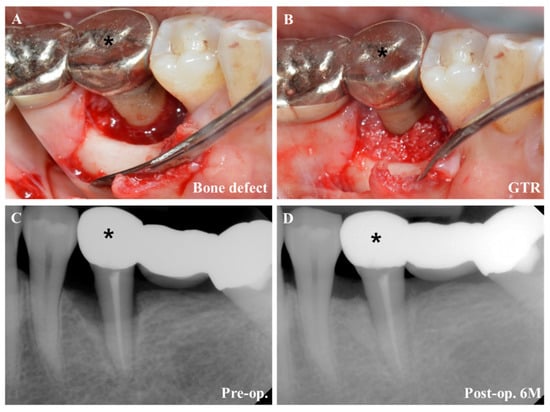

4.3. Regenerative Periodontal Surgery

- Smitha Annie Jacob, A.D. Guided tissue regeneration: A review. J. Dent. Health Oral Disord. Ther. 2017, 6, 67–73. [Google Scholar]